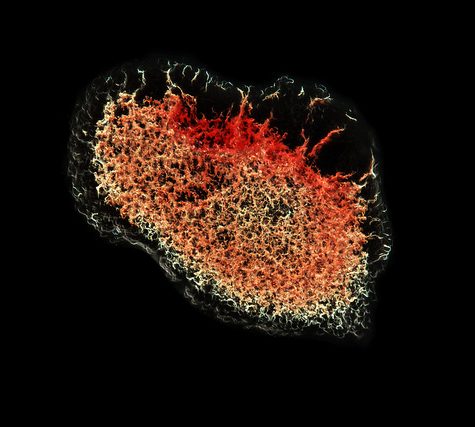

A thrombus, colloquially called a blood clot, is the final product of the blood coagulationstep in hemostasis. There are two components to a thrombus: aggregated platelets and red blood cells that form a plug, and a mesh of cross-linked fibrin protein. The substance making up a thrombus is sometimes called cruor. A thrombus is a healthy response to injury intended to prevent bleeding, but can be harmful in thrombosis, when clots obstruct blood flow through healthy blood vessels.

A thrombus, colloquially called a blood clot, is the final product of the blood coagulationstep in hemostasis. There are two components to a thrombus: aggregated platelets and red blood cells that form a plug, and a mesh of cross-linked fibrin protein. The substance making up a thrombus is sometimes called cruor. A thrombus is a healthy response to injury intended to prevent bleeding, but can be harmful in thrombosis, when clots obstruct blood flow through healthy blood vessels.